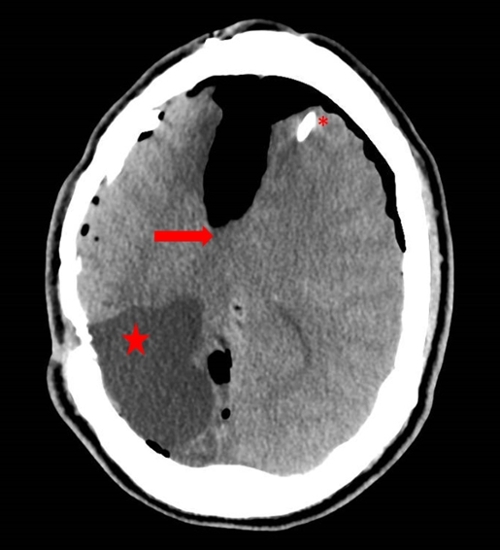

Fourteen years after his MVC, 13 years after initiation of CPAP therapy, and 12 years after his VP shunt placement the patient presented with the aforementioned headache. His physical exam on this presentation was notable for mild mental slowing and 1+ out of 5+ strength in both plantar and dorsiflexion of his left lower extremity. Computed tomography (CT) of the head was performed (Figure 1).

Figure 1: CT head showing acute changes associated with midline shift (arrow), ventriculo-peritoneal shunt (*), and encephalomalacia from prior right occipital hemorrhage (star).